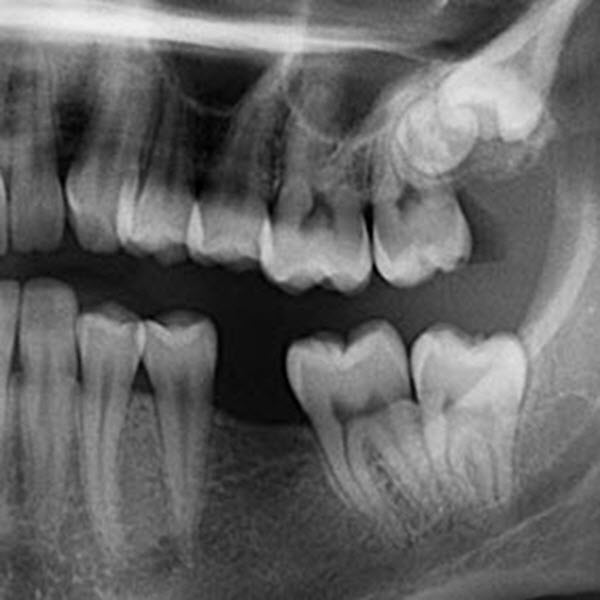

A dental crown is essentially a cap used to cover weak, decayed or broken teeth. If you have a tooth that is decayed to the point of cracking or breaking, a dental crown will likely be one option available to restore strength to the tooth. Dental crowns are affixed to the affected tooth with a hardening material that not only keeps…